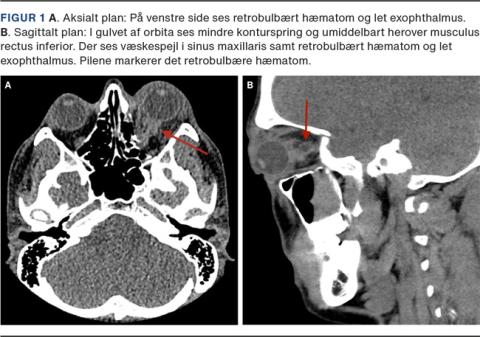

En 29-årig mand blev tilset i skadestuen efter at have været udsat for stump vold mod venstre øje. Ved ankomsten til skadestuen angav han begyndende hovedpine og sløret syn på øjet. Der blev rekvireret tilsyn ved en øjenlæge og bestilt CT af ansigtsskelettet. Ved øjenundersøgelsen fandtes øget retrobulbær resistance, påvirket n. opticus-funktion ved en relativ afferent pupildefekt påvist ved swinging flashlight-test og subkonjunktival blødning. CT’en viste venstresidig blowoutfraktur, udisloceret fraktur af orbitas medialvæg og retrobulbært hæmatom, hvilket medførte exophthalmus (Figur 1). I et samarbejde mellem en øre-næse-hals-kirurg og en øjenlæge blev der i skadestuen foretaget akut lateral kantotomi og inferior kantolyse under lokal infiltrationsanalgesi.